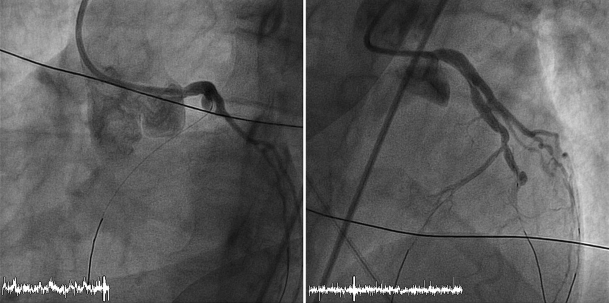

A coronary angiography of patient 1, showing occlusion of the left anterior descending artery distally from the first diagonal artery before and after treatment